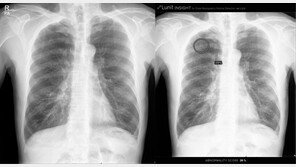

서울대병원은 독자 개발한 인공지능 기술을 1월부터 환자 영상 판독에 활용한다고 4일 밝혔다. 인공지능이 흉부엑스선 검사 영상을 보고 폐암 혹은 폐 전이암으로 의심되는 점을 알려줘, 자칫 놓칠 수 있는 폐암을 조기 진단할 수 있다. 인공지능 기반 영상판독 보조시스템 ‘루닛 인사이트…